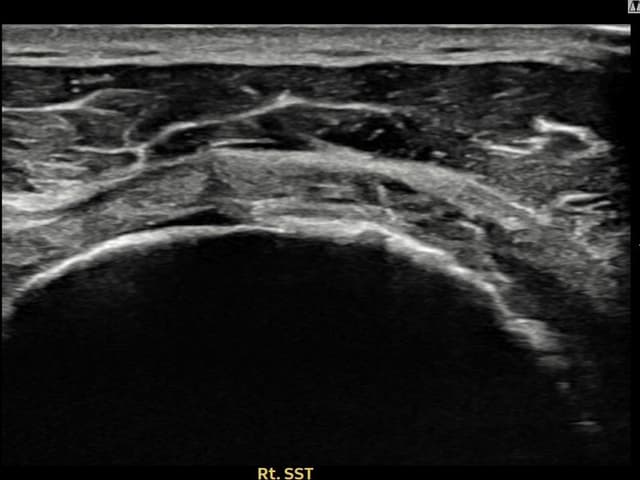

[촬영시기:21.09.27~21.10.07]

[석회분쇄흡입술] 우측 어깨의 야간 통증과 운동 제한으로 수개월간 고통받다 내원한 50세 남성 환자로, X-ray에서 극상근건 내 석회 침착이 확인되어 석회분쇄흡입술을 시행하였습니다.